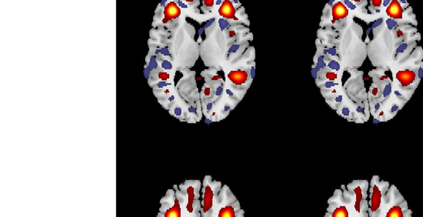

In the last two decades, unsupervised latent variable models---blind source separation (BSS) especially---have enjoyed a strong reputation for the interpretable features they produce. Seldom do these models combine the rich diversity of information available in multiple datasets. Multidatasets, on the other hand, yield joint solutions otherwise unavailable in isolation, with a potential for pivotal insights into complex systems. To take advantage of the complex multidimensional subspace structures that capture underlying modes of shared and unique variability across and within datasets, we present a direct, principled approach to multidataset combination. We design a new method called multidataset independent subspace analysis (MISA) that leverages joint information from multiple heterogeneous datasets in a flexible and synergistic fashion. Methodological innovations exploiting the Kotz distribution for subspace modeling in conjunction with a novel combinatorial optimization for evasion of local minima enable MISA to produce a robust generalization of independent component analysis (ICA), independent vector analysis (IVA), and independent subspace analysis (ISA) in a single unified model. We highlight the utility of MISA for multimodal information fusion, including sample-poor regimes and low signal-to-noise ratio scenarios, promoting novel applications in both unimodal and multimodal brain imaging data.